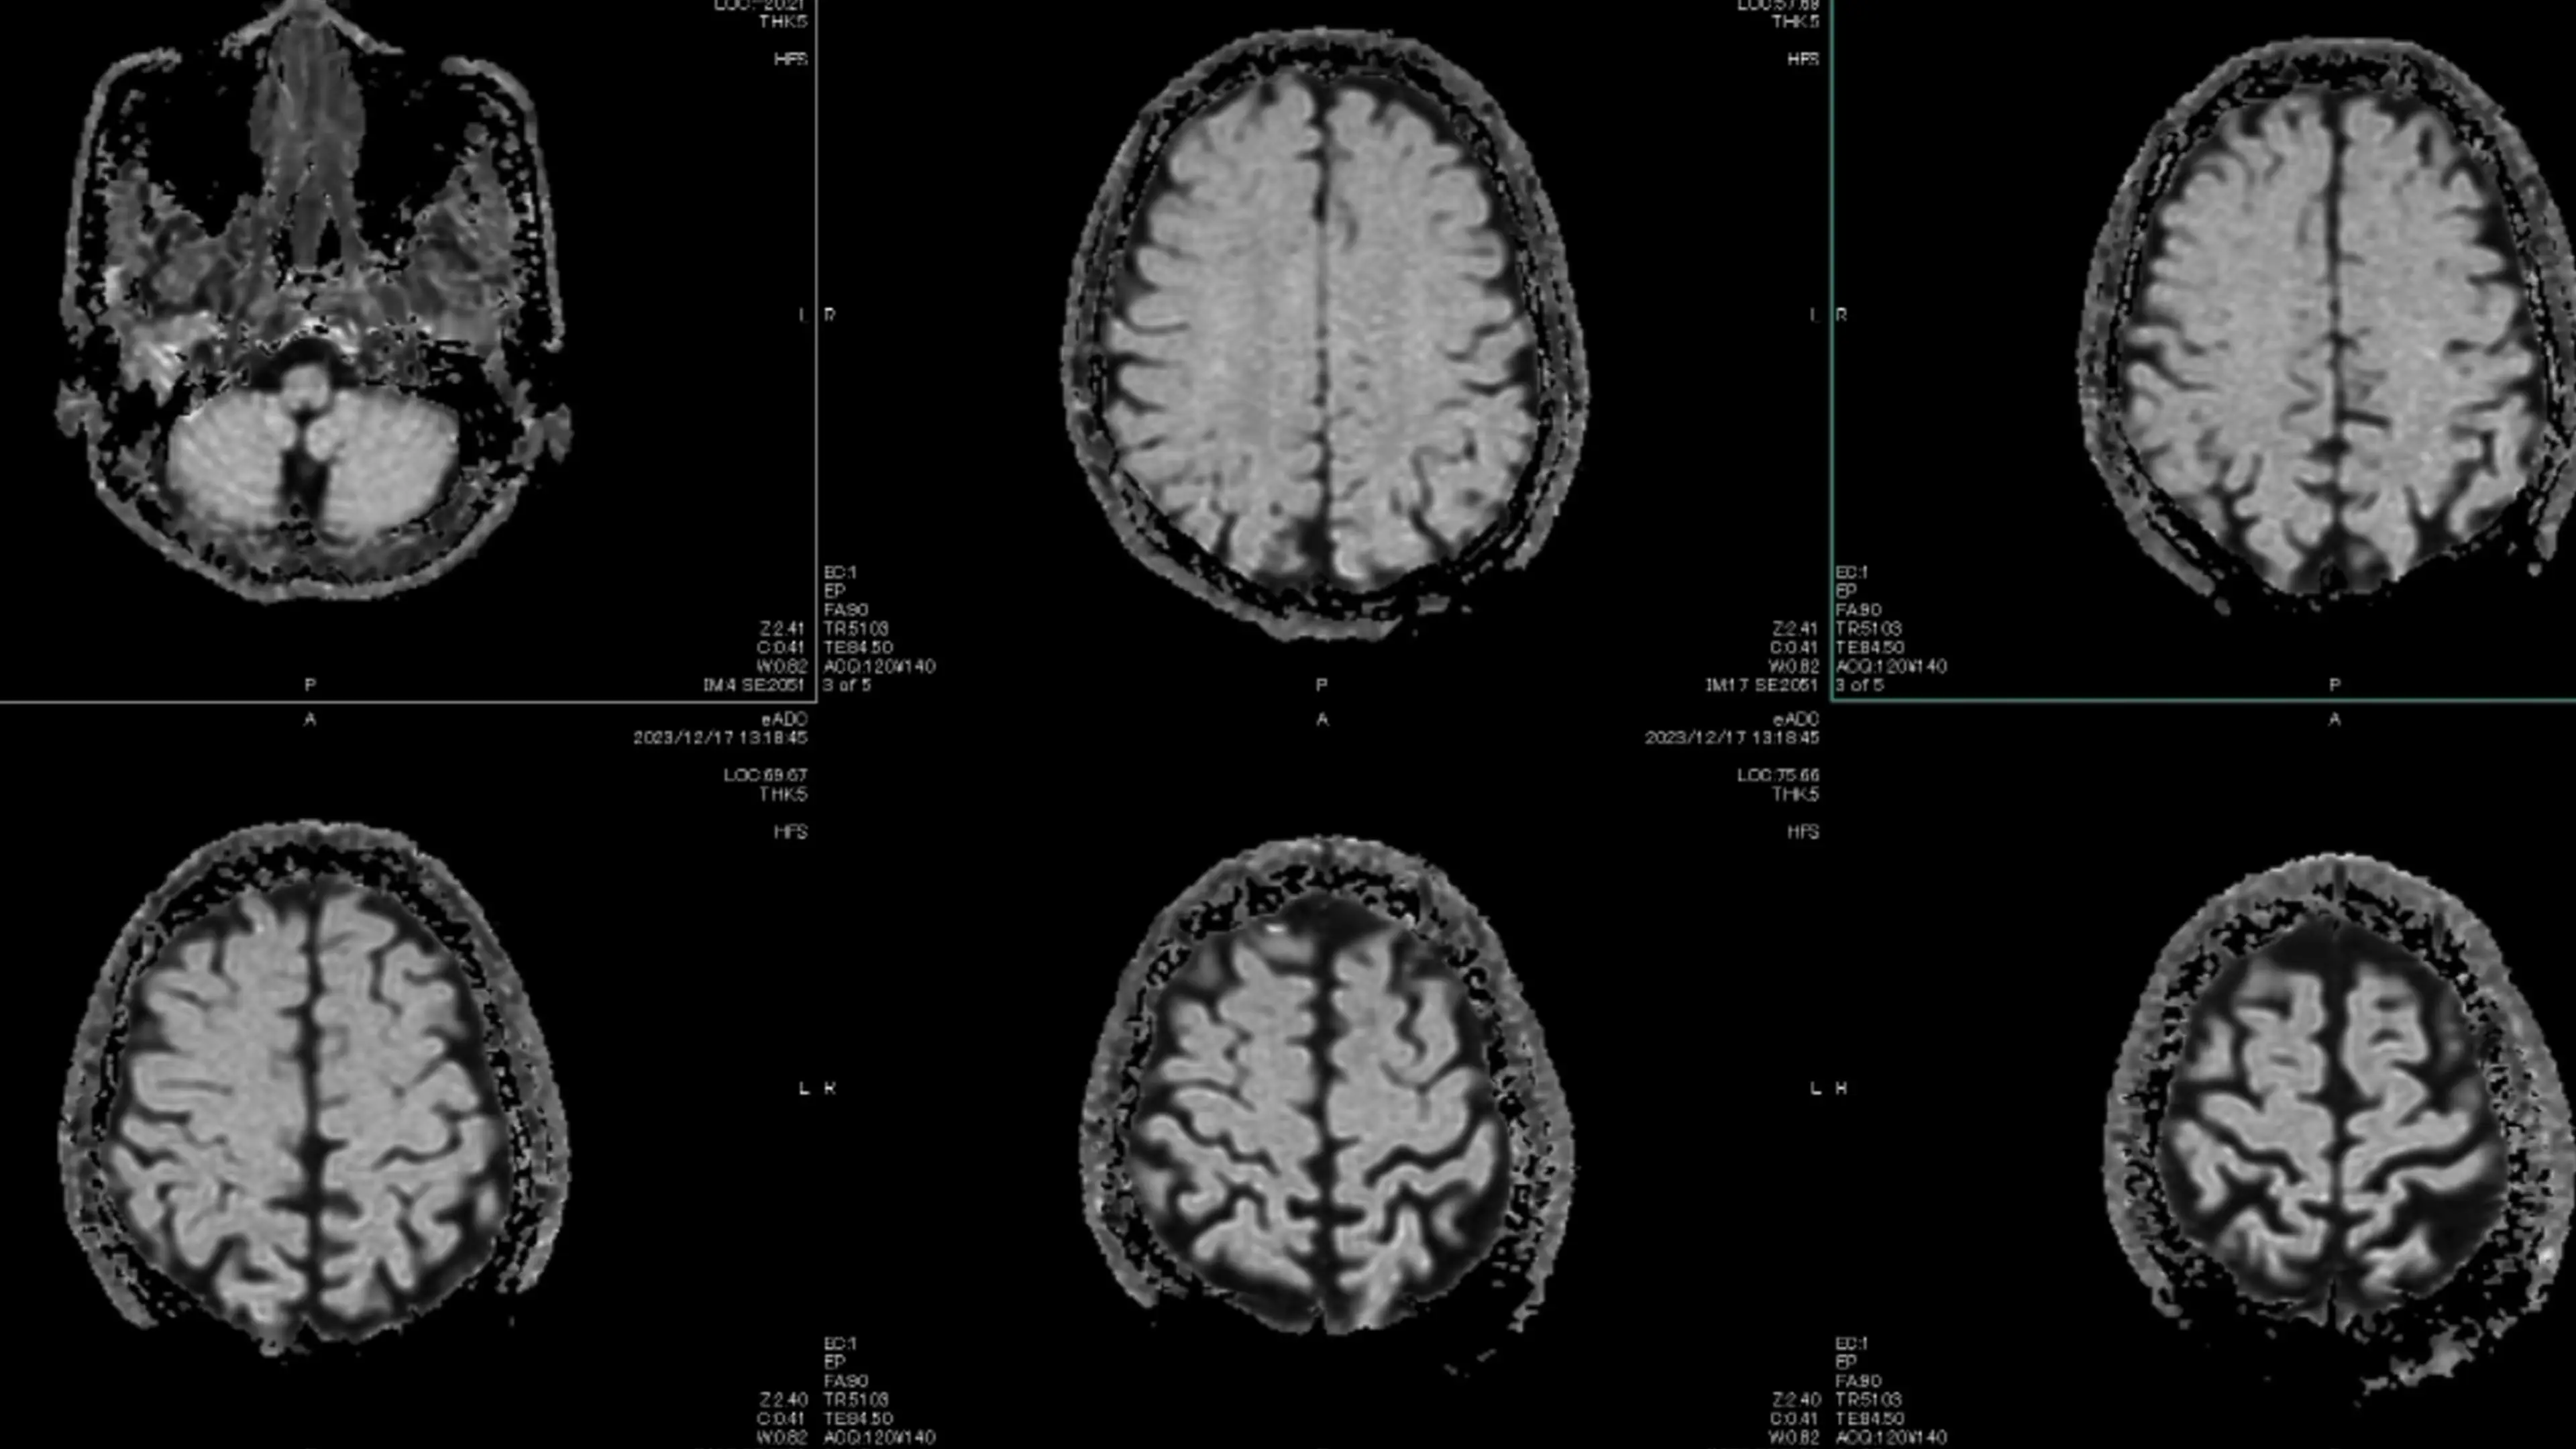

Five of the employees were diagnosed with benign tumors; three of which are reportedly brain tumors and two of which are meningiomas.

A meningioma 'is the most common type of tumor that forms in the head,' Mayo Clinic notes.

A meningioma 'grows from the membranes that surround the brain and spinal cord, called the meninges' and Mayo Clinic adds 'a meningioma is not a brain tumor, but it may press on the nearby brain, nerves and vessels'.